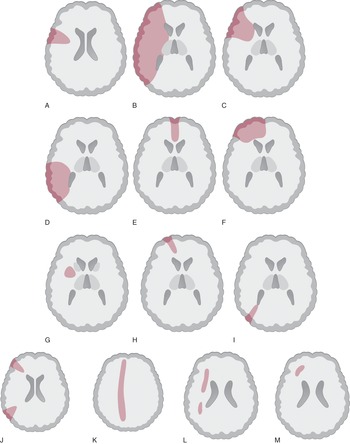

Clinical Neurology and Neuroanatomy: A Localization-Based, Large artery occlusive disease of the anterior circulation,